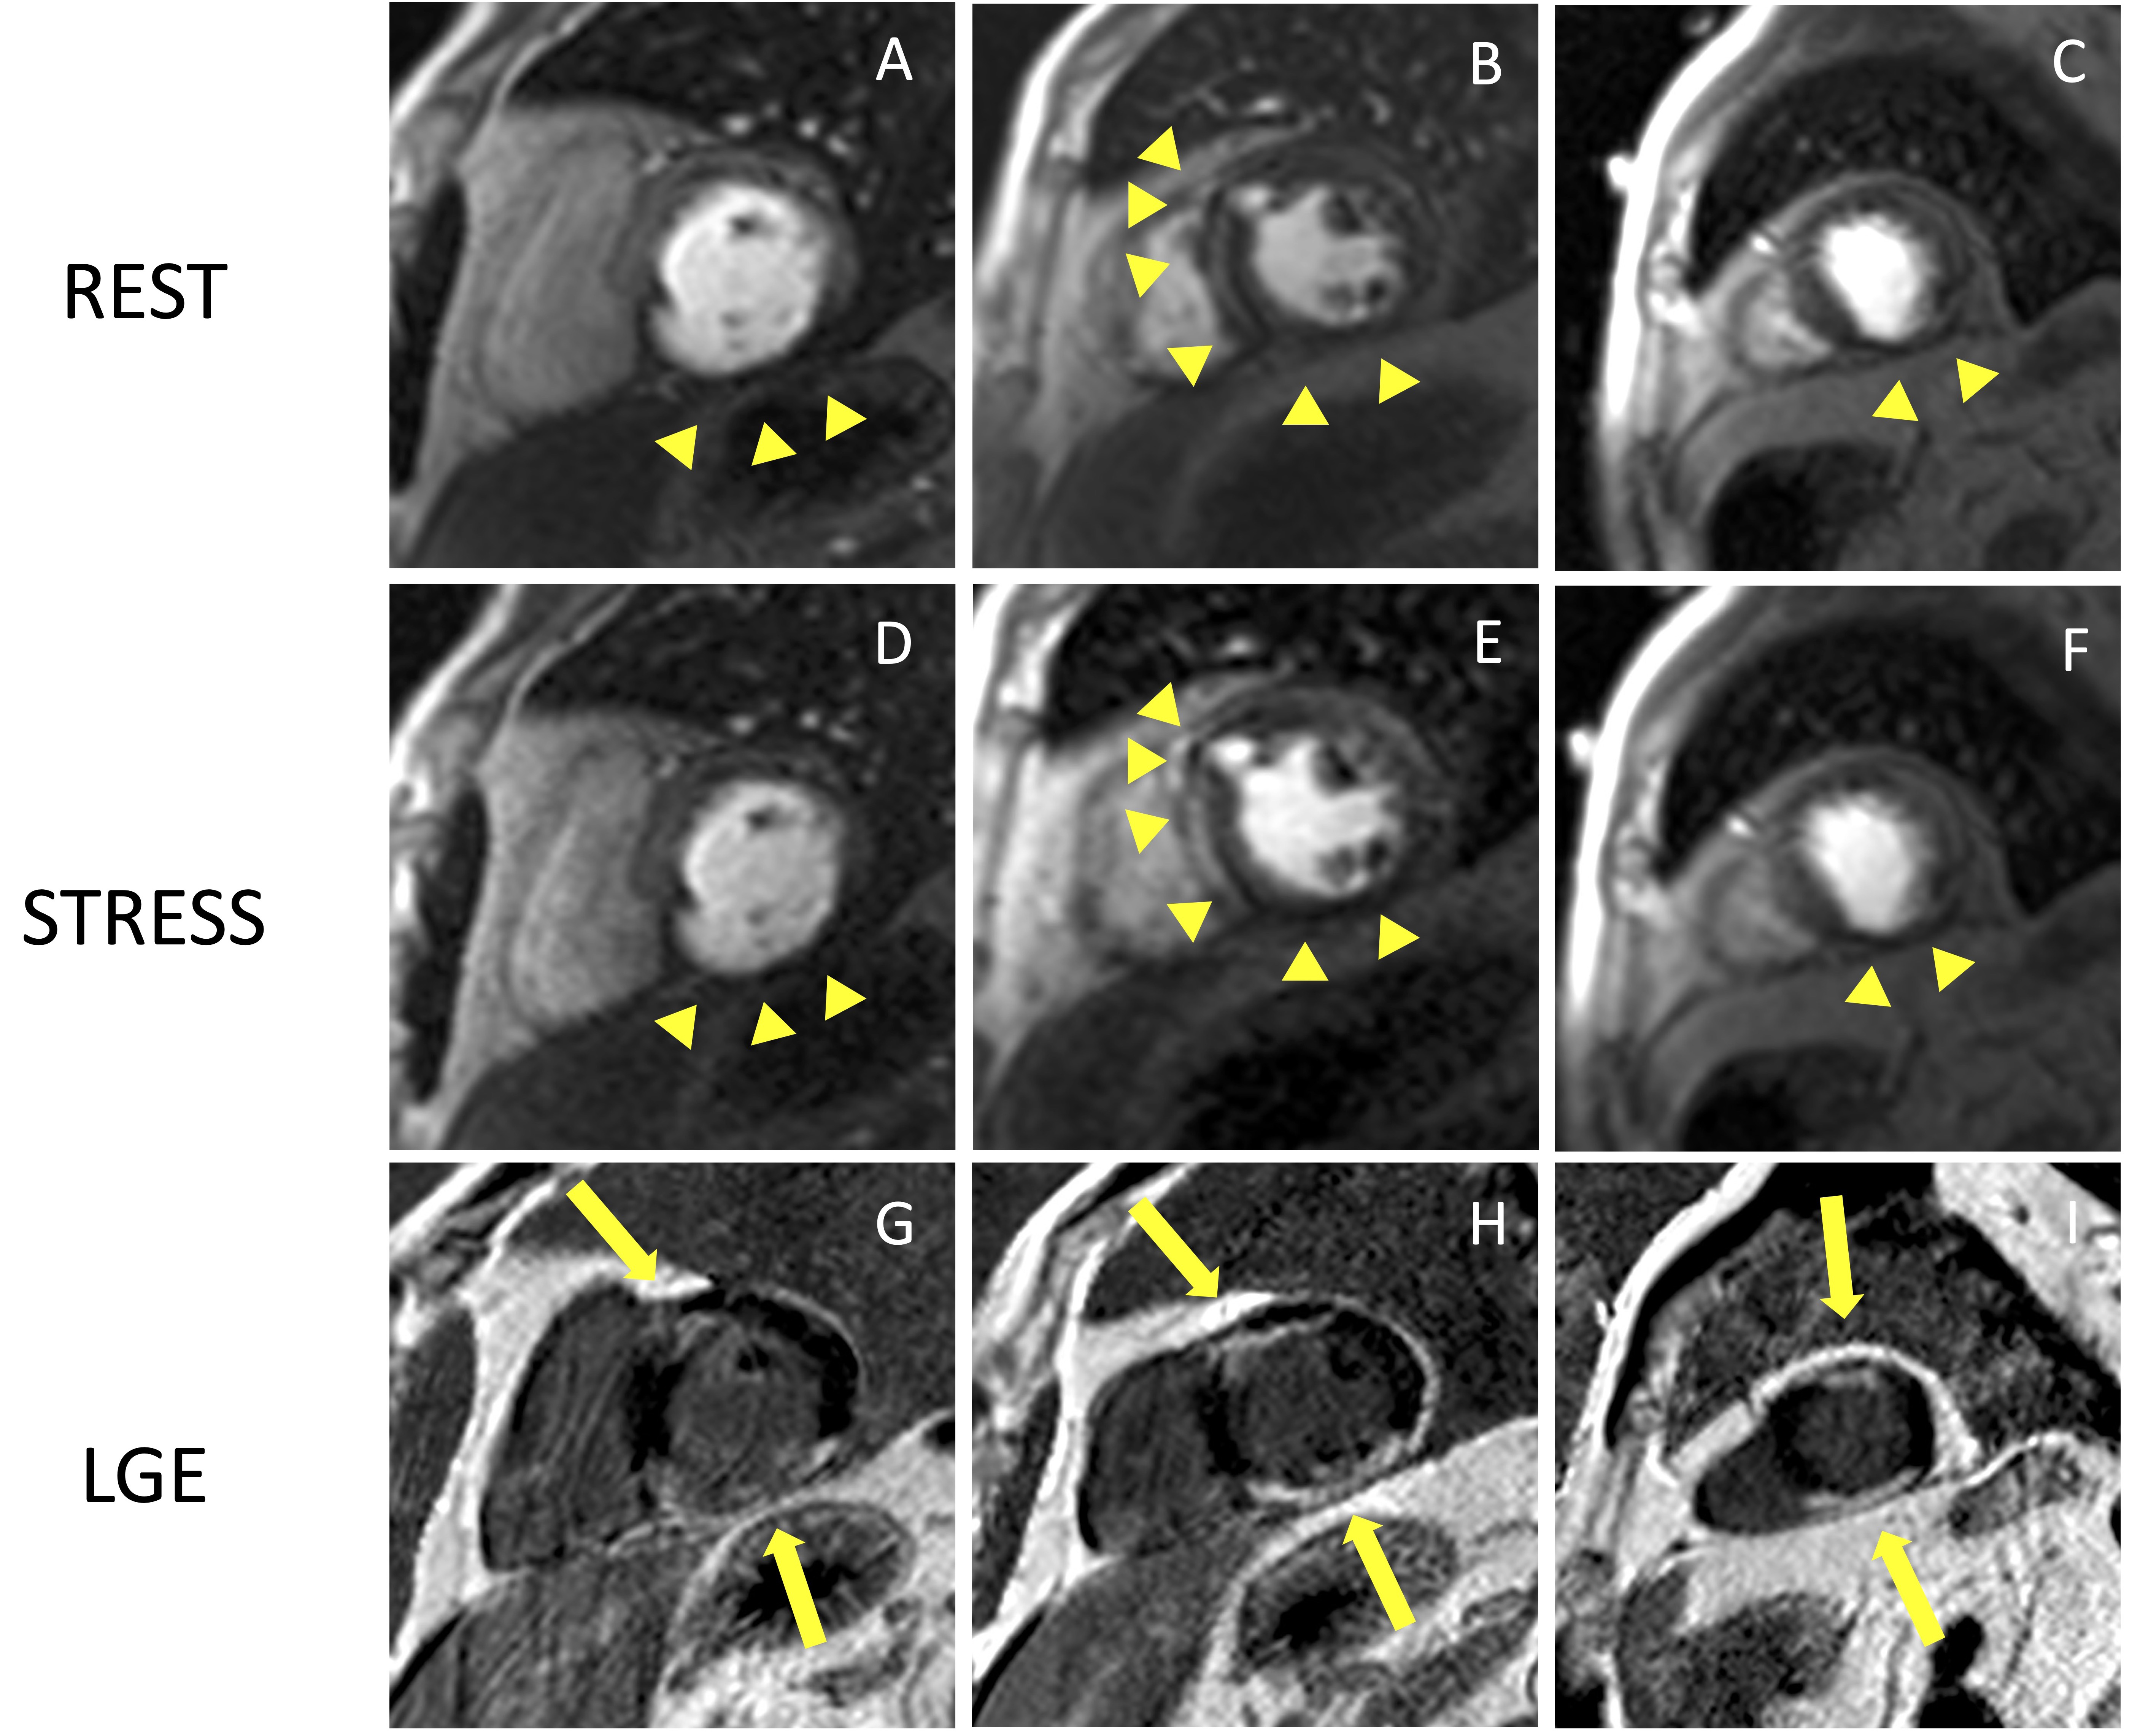

Stress CMR has been shown to be a safe and feasible technique, with good diagnostic quality. In a multicentre prospective registry of about 12,000 referral patients, stress CMR showed an excellent safety profile with higher incidence of mild complications and minor symptoms in dobutamine stress CMR compared to other vasodilators [33]. The safety of stress CMR has been demonstrated in patients with heart failure with reduced ejection fraction without any adverse event in a population of 1053 patients [34]. Stress CMR was well tolerated also in consecutive patients with MR-conditional pacemakers, with no significant change in lead thresholds or pacing parameters [35]. Pezel et al. [36] demonstrated the feasibility of vasodilator stress CMR in more than 600 patients with atrial fibrillation and suspected or stable coronary artery disease (CAD). Fig. 4 and Fig. 5 show two examples of stress CMR clinical cases. Fig. 6 shows how to implement stress CMR in clinical practice.

Fig. 5.

Fig. 5.Example of CMR adenosine-stress perfusion in the presence of

ischemic scar. This is the case of a 68-year-old man with a history of subacute

myocardial infarction and previous unsuccessful percutaneous angioplasty on the

RCA. Short axis rest and stress perfusion images are shown respectively at the

basal (A,D), mid-ventricular (B,E), and apical (C,F) level. There is

evidence of hypoperfusion, appearing as a hypointense subendocardial area in the

inferior septum, inferior wall and in the mid portion of the anterior wall

(yellow arrow heads). Corresponding LGE images (G,H,I) show ischemic scars

(yellow arrow lines) with a transmural distribution in the inferior septum and

inferior wall. Moreover, there is subendocardial LGE with a 50–75%

transmurality in the anterior wall. The perfusion defects appear both in the rest

and stress images and are related to the presence of non-viable myocardium (scar

transmurality